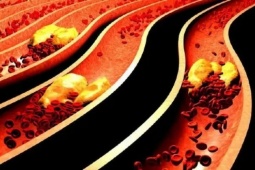

4 thói quen xấu dễ làm tắc nghẽn mạch máu, đặc biệt là điều cuối cùng